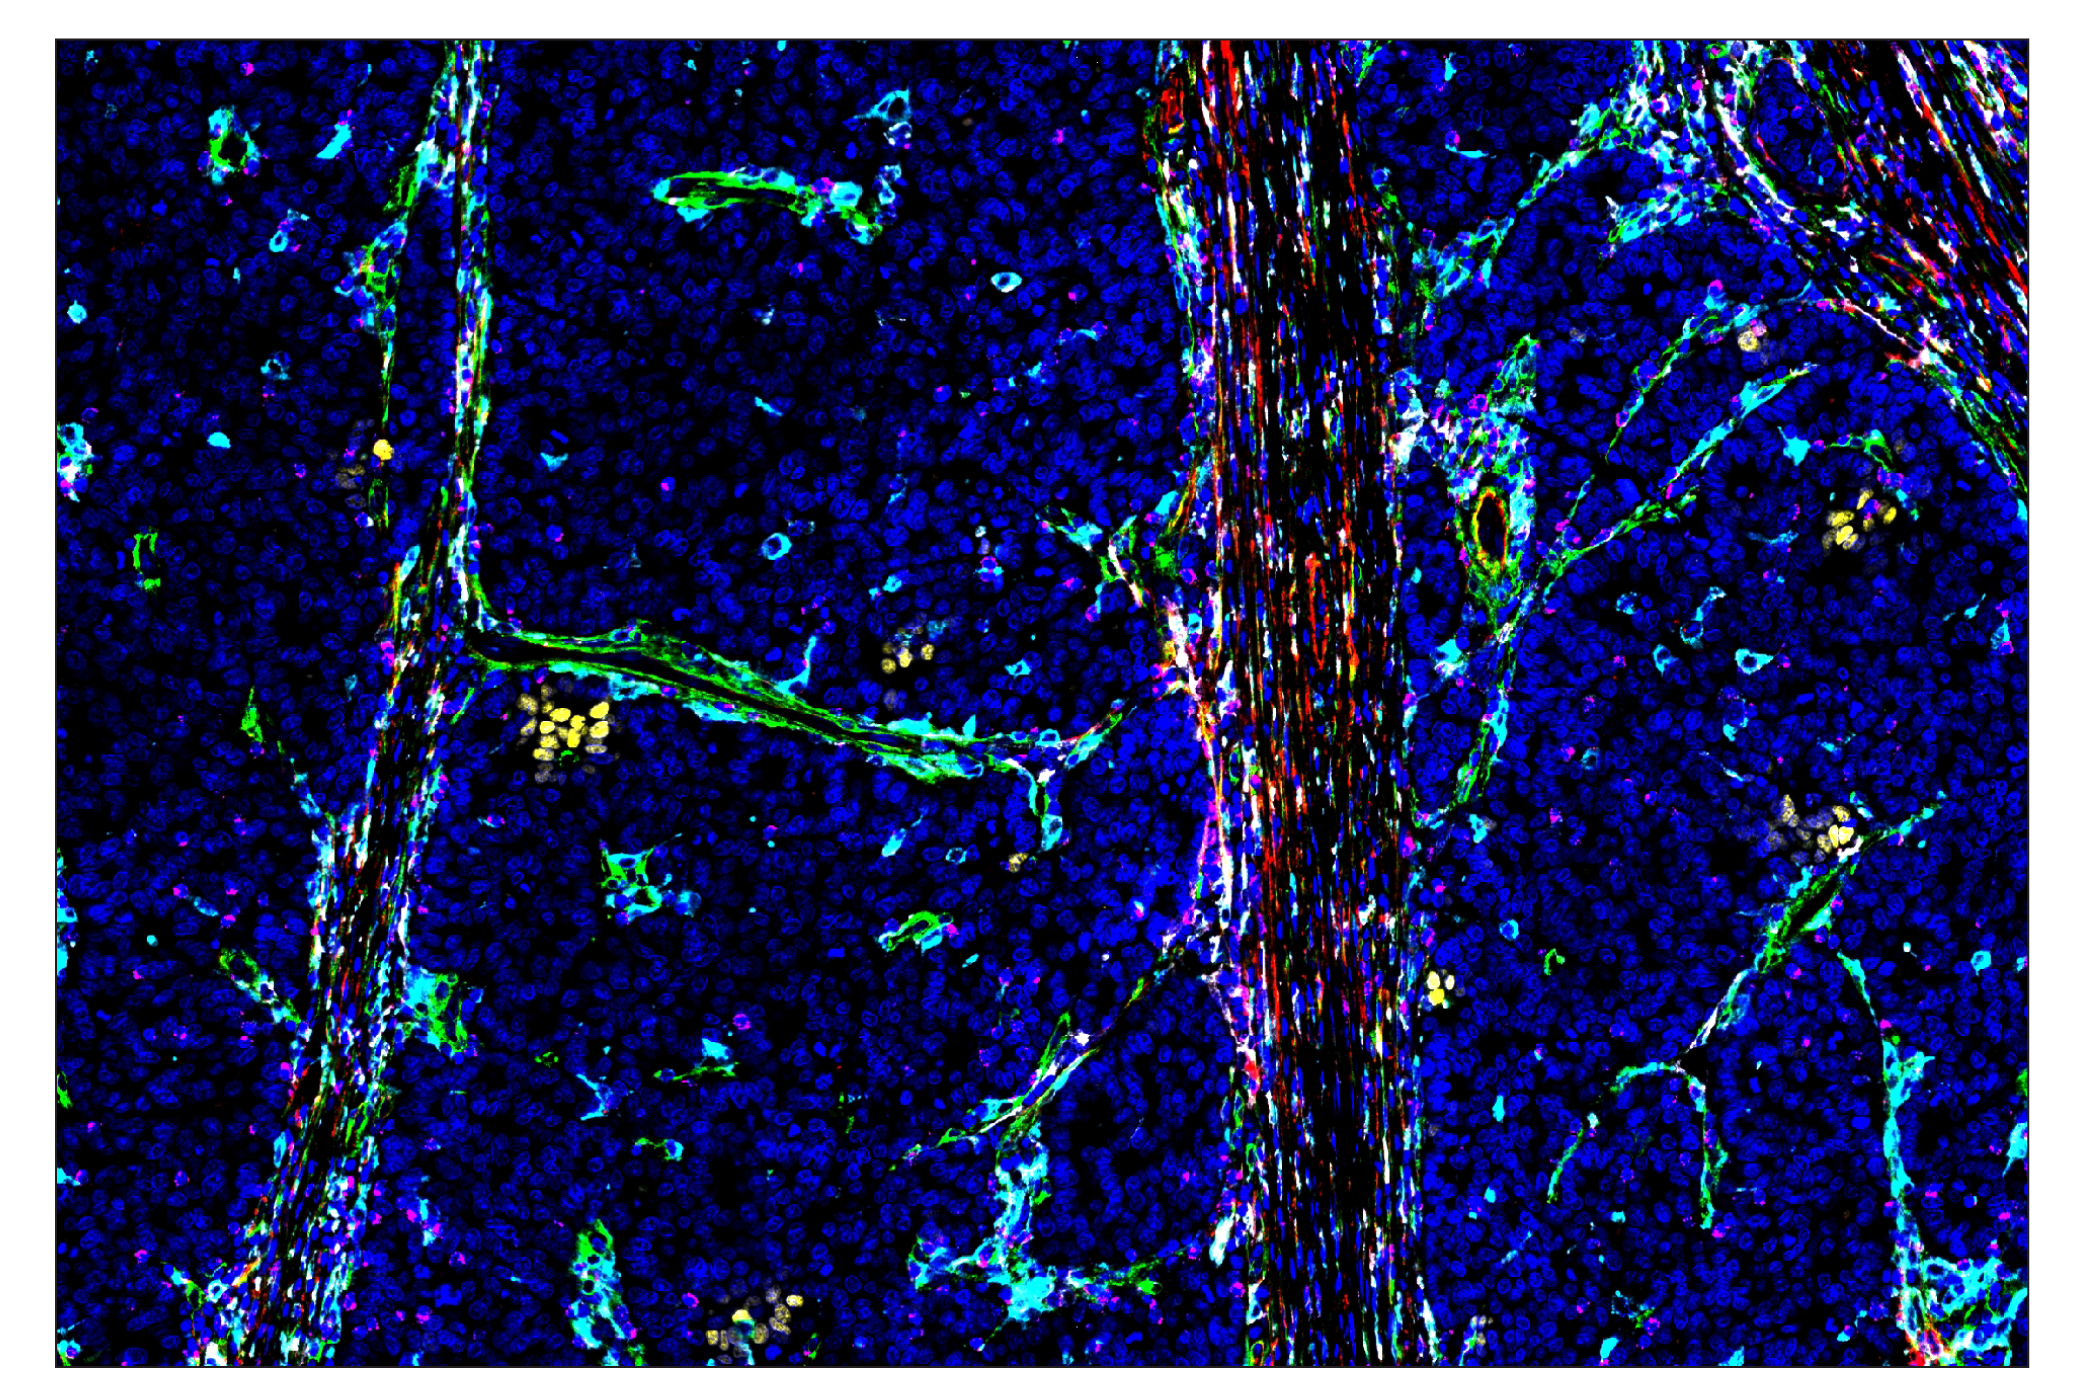

Phospho-Stat1 (Tyr701) (58D6) & CO-0196-594 SignalStar® Oligo-Antibody Pair #91016

SignalStar multiplex immunohistochemistry (IHC) is an advanced technology for labeling multiple proteins simultaneously in tissue samples using specific primary antibodies and fluorescent detection reagents. This technology offers accuracy and reliability in visualizing and analyzing protein expression while maintaining spatial context and tissue architecture.

Phospho-Stat1 (Tyr701) (58D6) Rabbit mAb (SignalStar® Conjugate 0196) detects endogenous levels of Stat1 only when phosphorylated at tyrosine 701. The antibody detects phosphorylated tyrosine 701 of p91 Stat1 and also the p84 splice variant. It does not cross-react with the corresponding phospho-tyrosines of other Stat proteins.